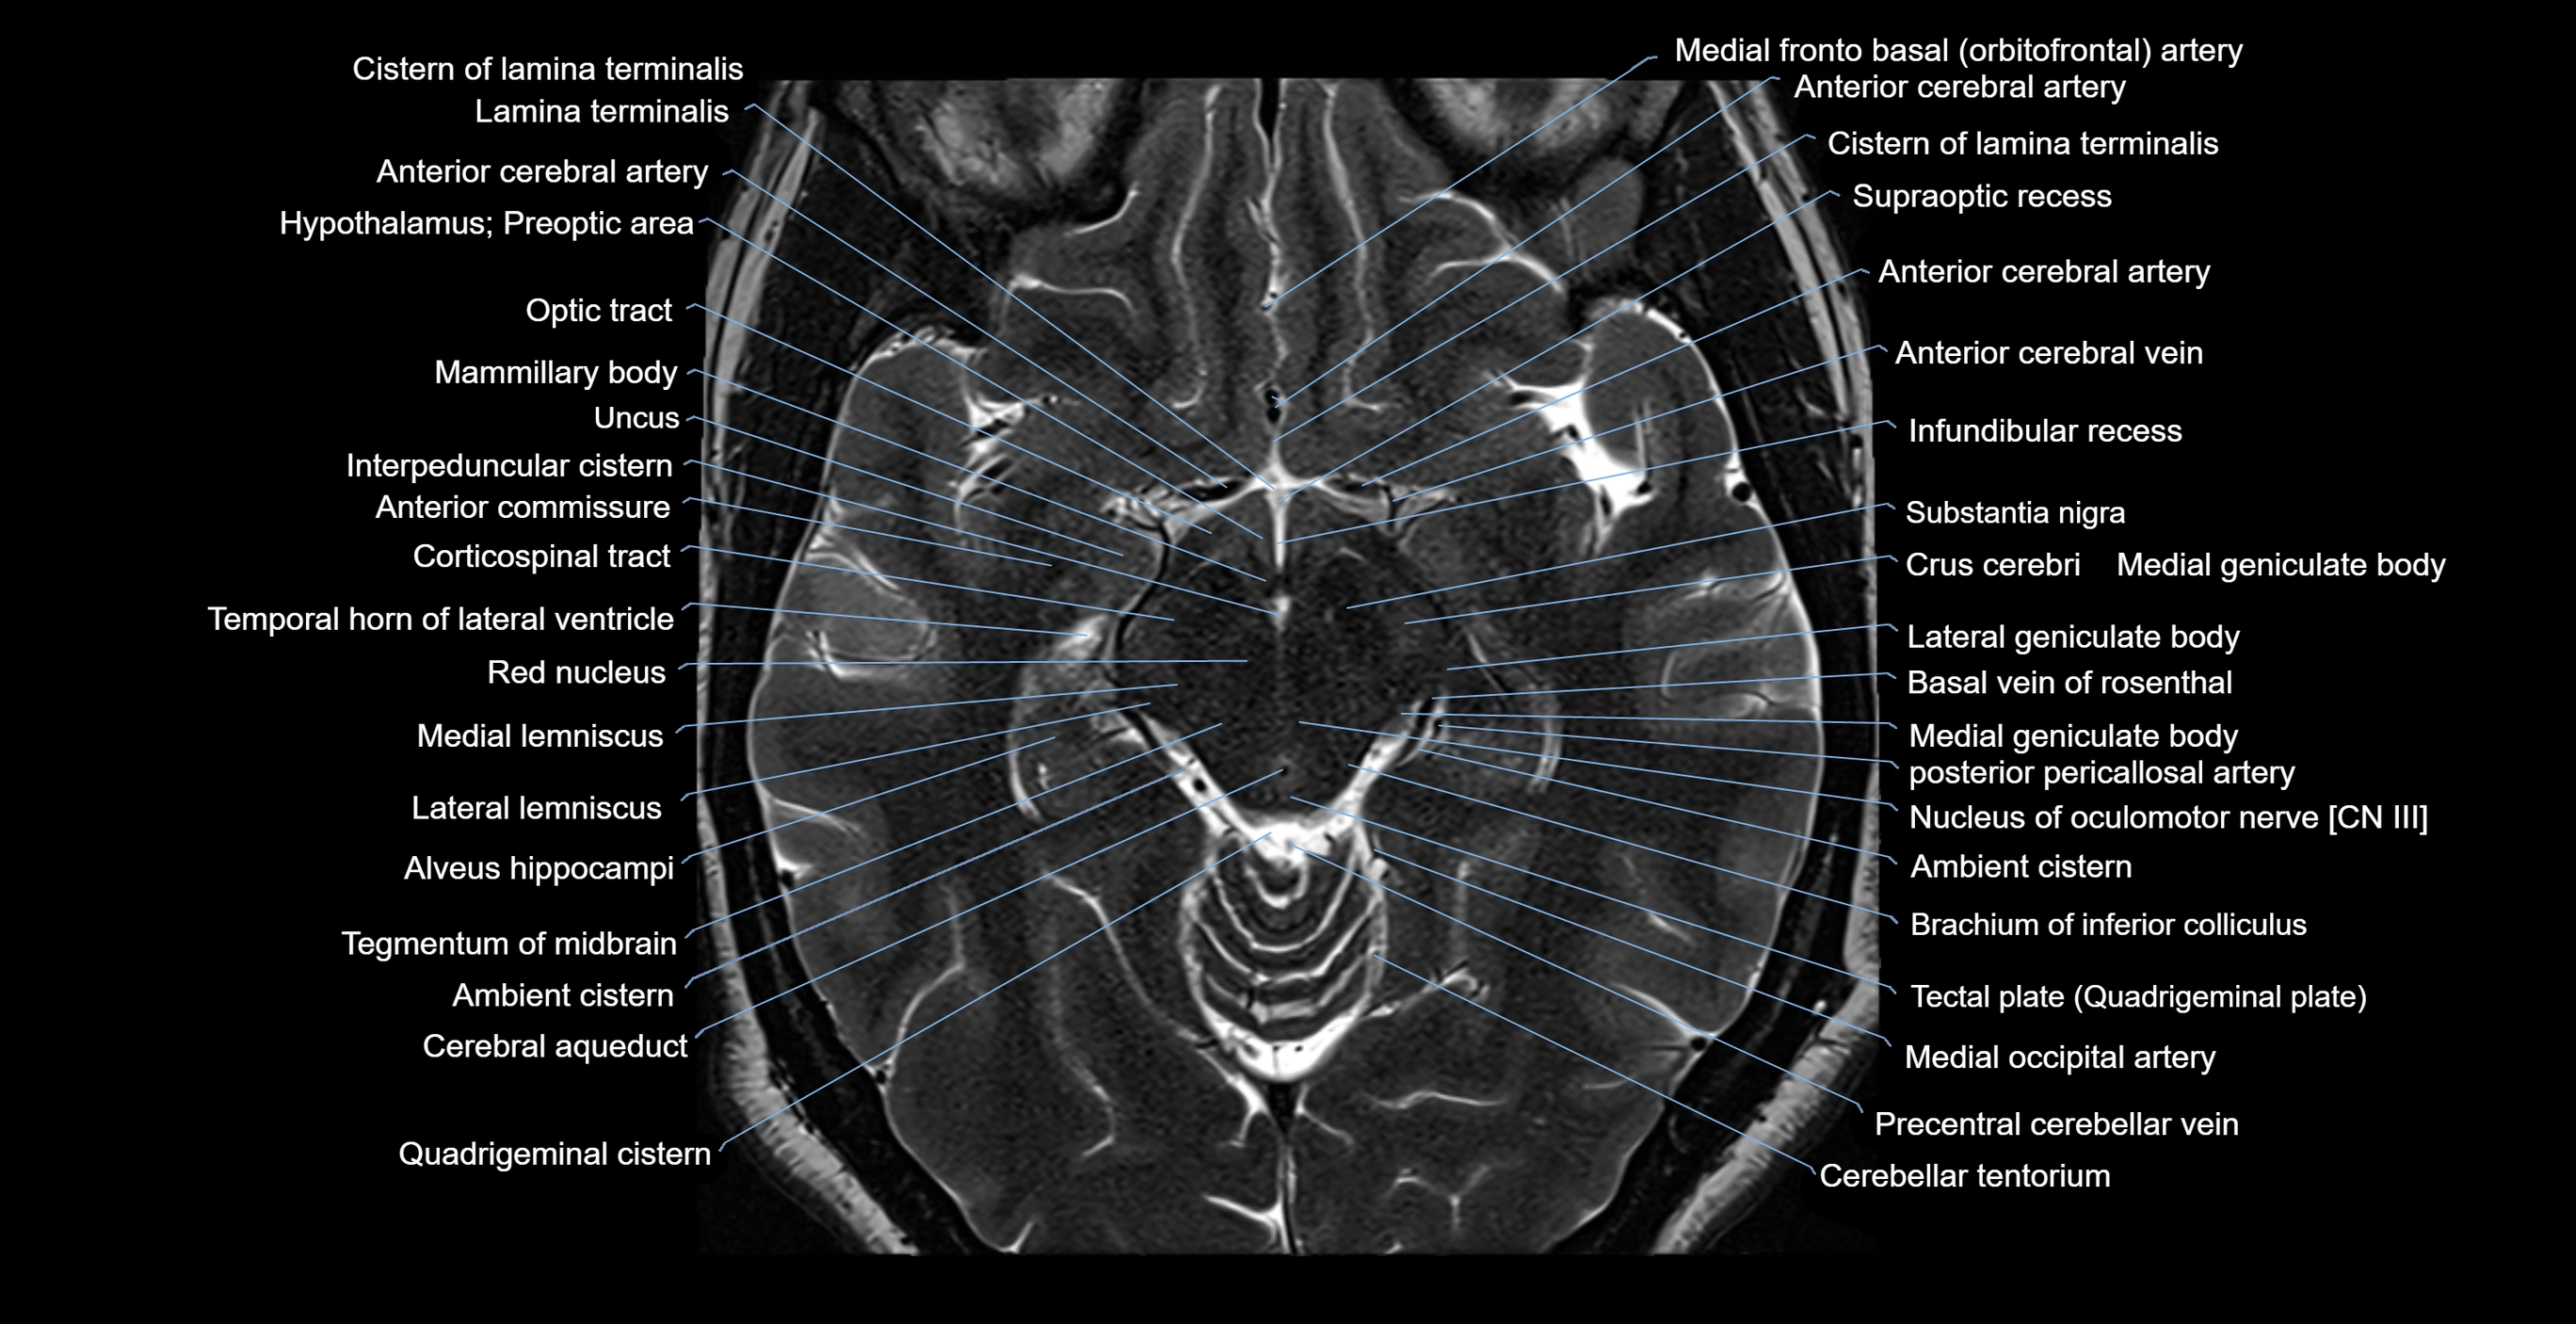

- Ambient cistern

- Brachium of inferior colliculus

- Cerebral aqueduct

- Corticospinal tract

- Crus cerebri

- Interpeduncular Cistern

- Lateral geniculate body

- Lateral lemniscus

- Mammillary body

- Medial lemniscus

- Nucleus of oculomotor nerve

- Optic tract

- Quadrigeminal cistern

- Red nucleus

- Substantia nigra

- Tegmentum of midbrain